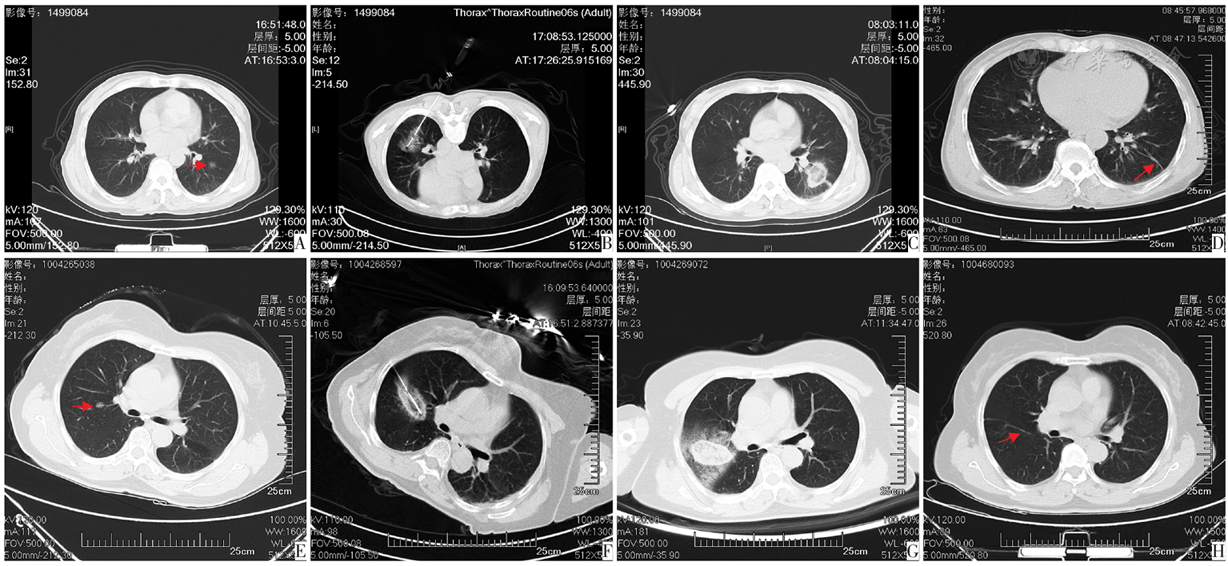

图1 肺结节微波消融和冷冻消融治疗前后CT图像。图A-D为肺结节微波冷冻消融治疗前后CT影像,图A为患者64岁,女,2021年3月胸部CT检查左下肺背段见一大小为10 mm亚实性磨玻璃结节;图B为左下肺背段结节CT引导下经皮肺穿刺微波消融术;图C为微波消融术后即刻复查胸部CT形成的晕征;图D为微波消融术后3年复查胸部CT仅遗留一纤维化病灶,肿瘤未复发。图E-H为肺结节冷冻消融治疗前后CT影像;图E为患者60岁,女,2022年10月胸部CT平扫示右上肺后段大小10 mm磨玻璃结节;图F为CT引导下经皮肺穿刺冷冻消融术;图G为冷冻消融术后即刻复查胸部CT形成的晕征;图H为冷冻消融术后3年复查胸部CT纤维化病灶较2年减缩小,肿瘤未复查